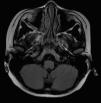

La resonancia magnética craneal mostraba ocupación de celdillas etmoidales con engrosamiento mucoso maxilar bilateral y esfenoidal de etiología inflamatoria (fig. 1). Se realizaron potenciales evocados visuales y examen oftalmológico que resultaron normales, así como el hemograma y la bioquímica general.